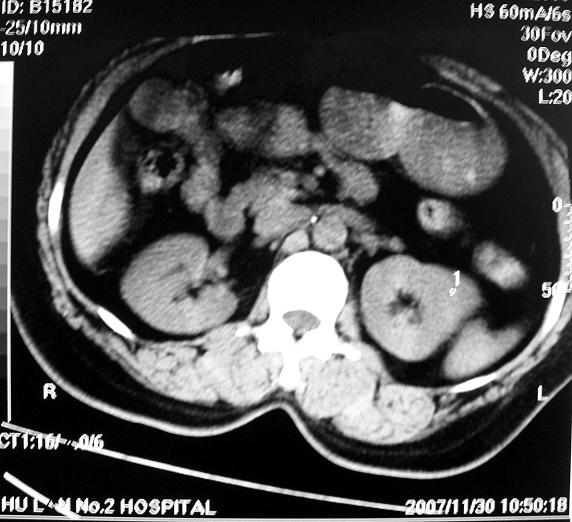

标题: CT10687:肾脏CT,请会诊

女,53岁,尿频尿急来诊,其他层面无异常未上传。

肾柱肥大可能?请增强结合b超

像是一个正常的驼峰样改变!!不放心就做个增强

应该是正常的表现!左肾上极外侧变异较多;建议增强!

正常!日常检查中多有肾驼峰状改变,为正常变异

应该是正常的表现!建议增强,胃腔怎么是实性表现,请传全图象!